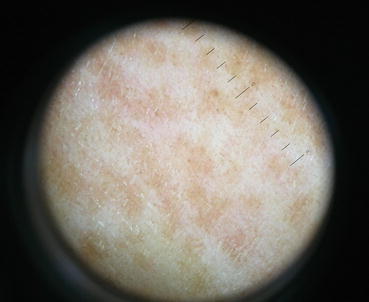

Fig. 22.1

Retention of perifollicular pigmentation in early lesion of vitiligo